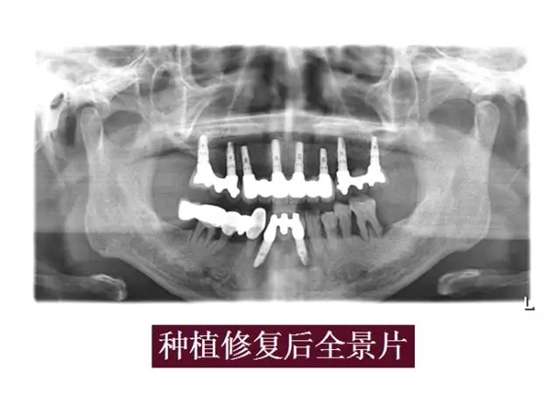

自體牙骨粉病例展示: